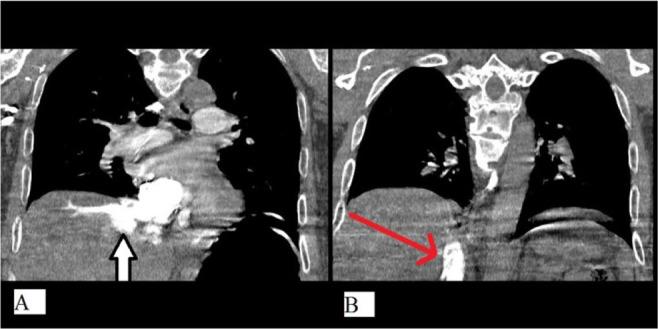

Pulmonary thromboembolism following spine surgery, although rare, could end into devastating outcome. Gold standard for it diagnosis is pulmonary CT angiography but in operating theatre, clinical suspicion is the key to diagnose. Here we report a case of pulmonary embolism with classic clinical findings which approved using pulmonary CT angiography and echocardiography.

脊柱手术后发生肺血栓栓塞症,虽然罕见,但可能导致灾难性后果。其诊断的金标准是肺部CT血管造影,但在手术室中,临床怀疑是诊断的关键。在此我们报告一例具有典型临床症状的肺栓塞病例,该病例经肺部CT血管造影和超声心动图得以确诊。